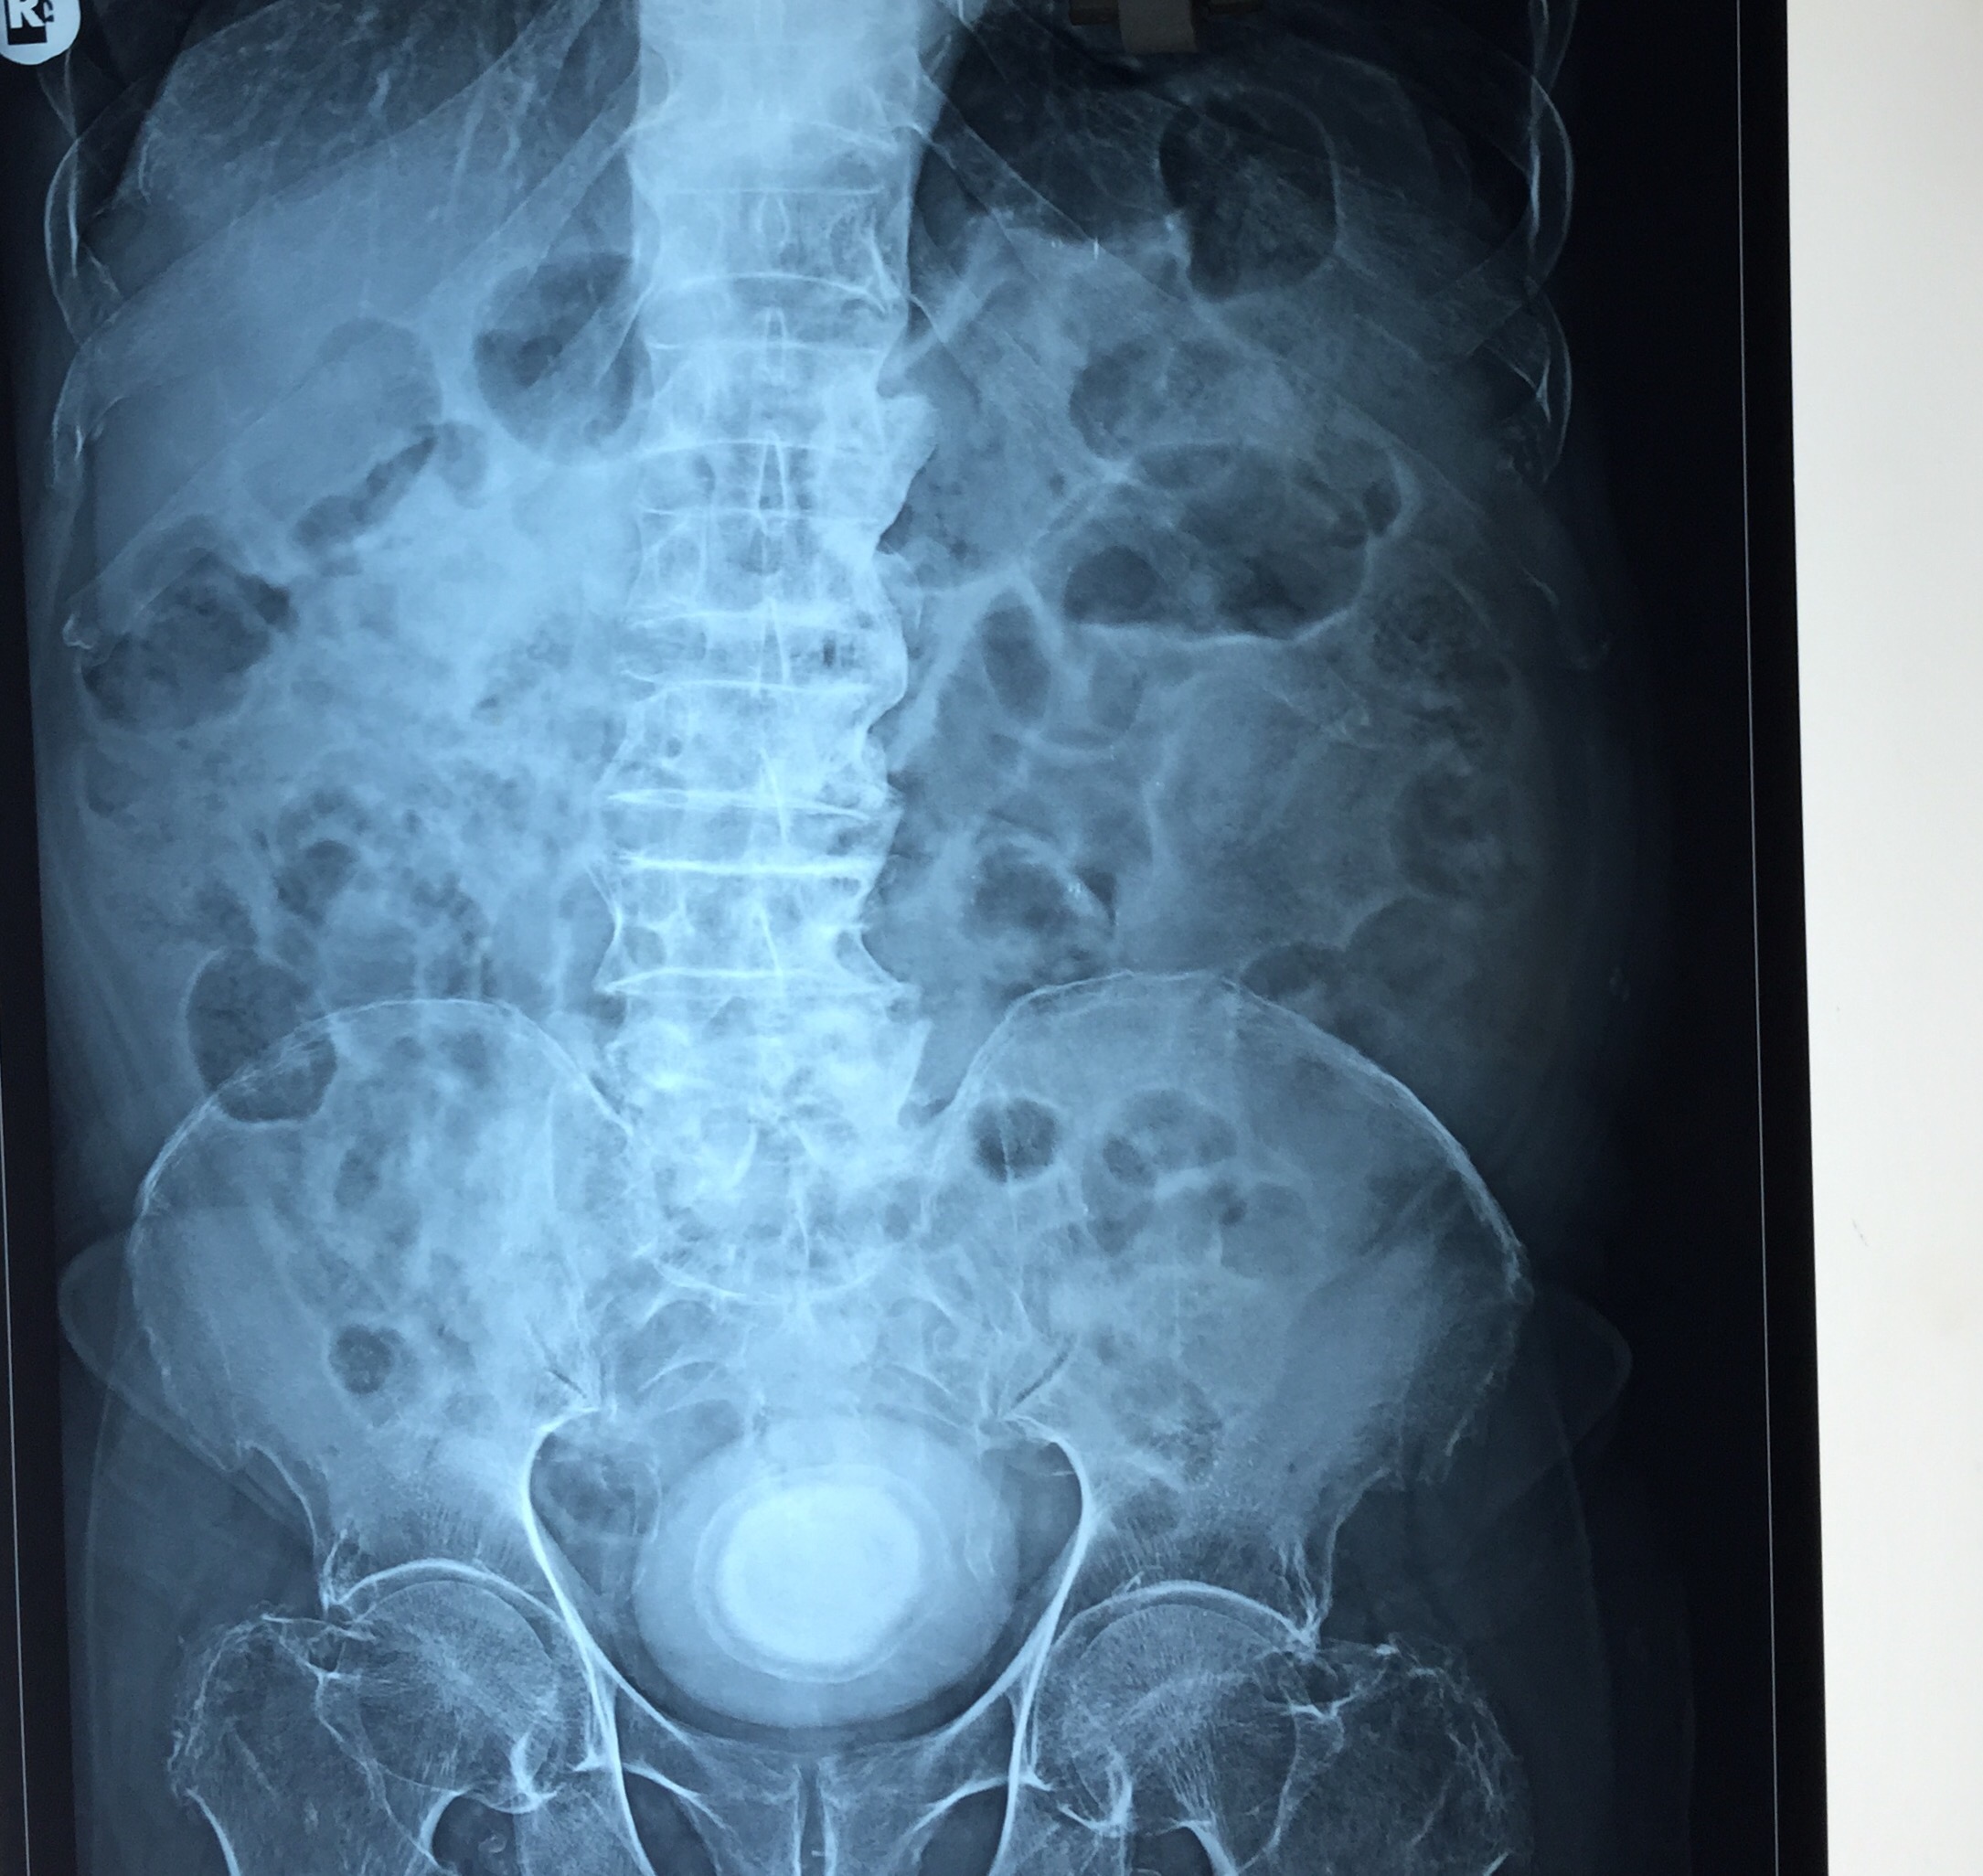

CT scan confirmed the ultrasound findings :

LARGE CALCULUS IN THE URINARY BLADDER WITH MULTIPLE DIVERTICULAE IN THE BLADDER “

The X-ray and the CT scan pictures are given below.